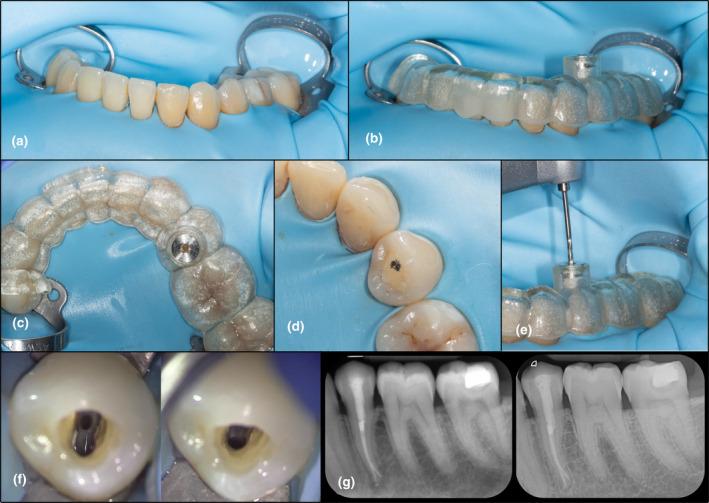

This trial was registered in the ISRCTN.com registry (ISRCTN75277265) and designed as a controlled clinical trial: Single arm trial, prospective, nonrandomized, single-centre study (ethical approval number S64630). Inclusion criteria were; tooth presenting with PCO and symptoms and/or signs of apical periodontitis (AP). An external control group was selected from clinical records of patients presenting the same criteria but treated freehanded. Guided root canal treatments were performed by the same operator on all patients. Freehanded treatments were performed by a specialist in endodontics under microscope with pre-operative CBCT available. Primary outcome for both groups was evaluated as: canal found, canal not found, or perforation. As secondary outcome, the qualitative accuracy of the drill path was assessed as: optimal precision, acceptable precision or technical failure. Patients were followed up yearly. Descriptive statistics on the study patient's demographics and healing outcome were performed and specific statistical analysis was performed on each outcome variable.

A total of 133 teeth were included (n = 60 guided, n = 73 freehanded) from 128 patients (n = 59 guided, n = 69 freehanded). The primary outcome for the guided group was: 59 teeth canals found and 1 tooth canal not found. No perforations were recorded. In the freehanded group, the root canal was successfully found in 59 teeth, seven were not found, and seven had a perforation. An analysis of all data showed that guided endodontics presented statistically significant better outcome than freehand treatment (p < .05).